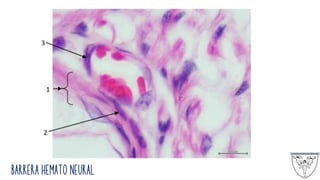

Barrera Hemato Neural

El perineuro funciona como una barrera de difusión

metabólicamente activa que contribuye a la formación de la

barrera hematoneural (hemato-nerviosa)

Esta barrera mantiene el medio iónico de las fibras nerviosas

envainadas. Las células plerineurales poseen receptores,

transportadores y enzimas que proveen el transporte activo de

sustancias.

Las células que componen esta capa son escamosas, son

contráctiles y contienen una cantidad apreciable de filamentos de

actina. También se hallan fibras de colágeno y posee uniones

estrechas